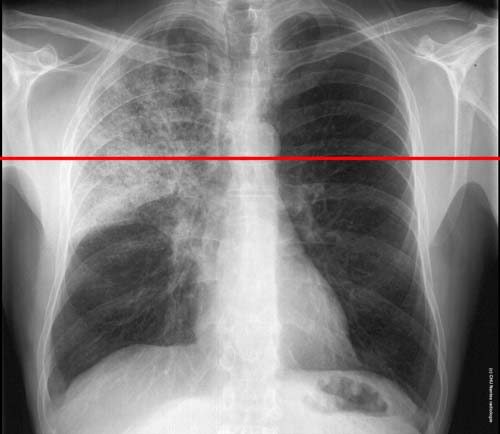

Syndrome interstitiel en rayon de miel :

niveau de la coupe TDM